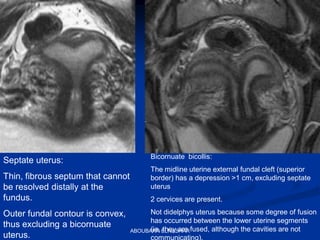

Septate uterus:

Thin, fibrous septum that cannot

be resolved distally at the

fundus.

Outer fundal contour is convex,

thus excluding a bicornuate

uterus.

Bicornuate bicollis:

The midline uterine external fundal cleft (superior

border) has a depression >1 cm, excluding septate

uterus

2 cervices are present.

Not didelphys uterus because some degree of fusion

has occurred between the lower uterine segments

(ie, they are fused, although the cavities are not

communicating).